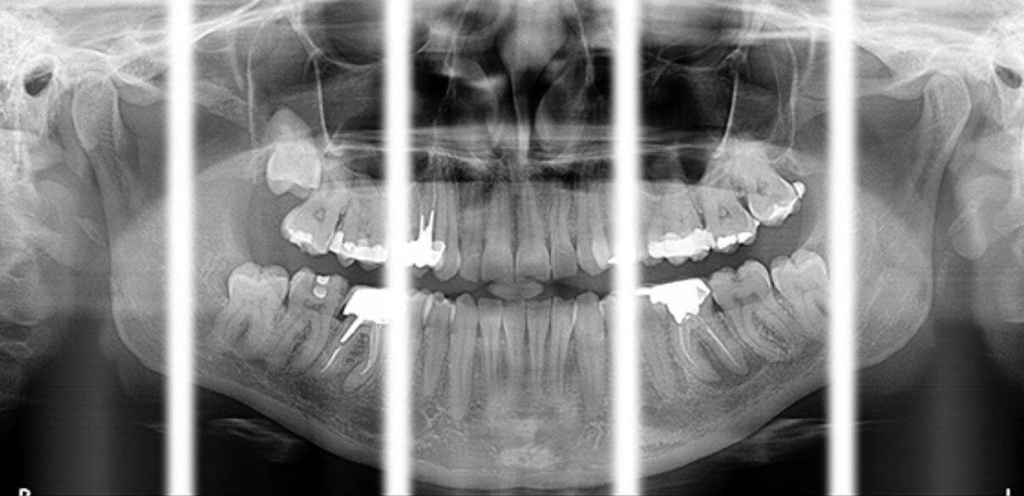

This next-gen model expands your field of view options for unparalleled flexibility. With nine selectable views ranging from 4x4 cm all the way up to 12x10 cm, the CS 8200 is equipped to cover virtually any diagnostic need your practice requires.

The CS 8200 3D blends 2D panoramic technology, CBCT imaging and 3D model scanning to create one powerful unit.

The CS 8200 3D offers multiple fields of view, to support all of your diagnostic needs — from routine exams to specialized ones.

This all-in-one unit is designed to seamlessly capture stunning 2D panoramic views and medium field of view 3D cone beam scans with ease. With a wide range of medium to large field of view settings from 4x4 cm up to 12x10 cm, the CS 8200 supports an impressive variety of specialized dental applications.

Whether you need detailed bitewing analysis, full jaw visualization, or targeted higher resolution imaging, this system's adaptable field of view has you covered. And as your practice grows, simply upgrade to add cephalometric capabilities for even greater clinical flexibility.